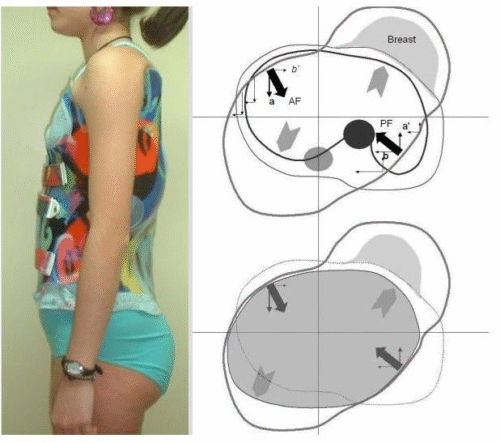

الدراسات أظهرت أن نقص الوزن يقلل من قدرة الحزام الطبي على تقويم العمود الفقري. السبب بسيط: العضلات والأنسجة الداعمة تكون أقل سمكًا، ما يجعل الحزام أقل ثباتًا على الجسم. وبالتالي تقل قدرته على توجيه العمود الفقري بشكل صحيح.

التطور الكبير في تصميم الأحزمة الطبية جعل علاج اعوجاج العمود الفقري عند المراهقين أكثر نجاحًا وأقل إزعاجًا. باستخدام تقنيات التصوير الثلاثي الأبعاد والمحاكاة الرقمية، أصبح الحزام أكثر خفة وراحة، ويعطي نتائج أفضل في تصحيح الانحناء والتواء العمود الفقري.